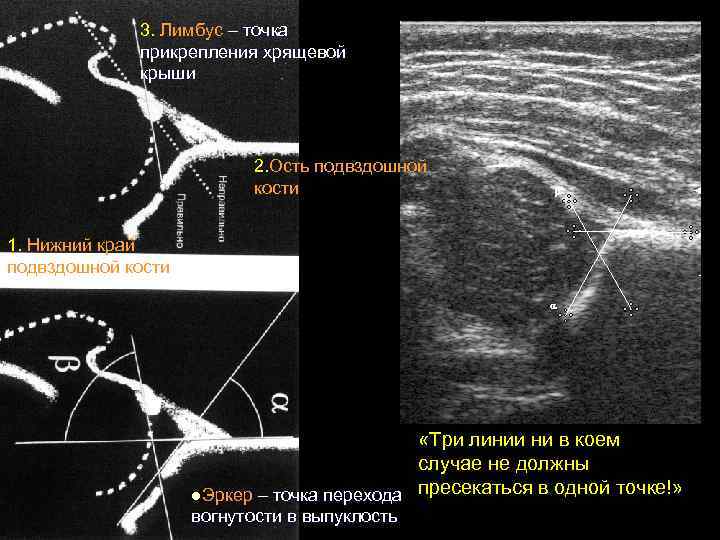

3. Лимбус – точка прикрепления хрящевой крыши 2. Ость подвздошной кости 1. Нижний край подвздошной кости «Три линии ни в коем случае не должны l. Эркер – точка перехода пресекаться в одной точке!» вогнутости в выпуклость